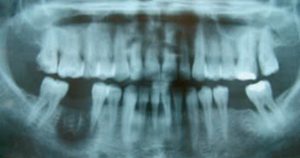

Trước đây, thạch tín từng được sử dụng trong nha khoa để làm chết tủy với các trường hợp viêm tủy cấp, đau dữ dội nhưng gây tê không hiệu quả. Đây chỉ là giải pháp mang tính tạm thời trong giai đoạn y học còn hạn chế. Về bản chất, thạch tín là một chất độc và chỉ định dùng với liều rất nhỏ, phải đặt đúng buồng tủy và giới hạn thời gian nghiêm ngặt (không quá 2-3 ngày), bác sĩ phải tư vấn rất kỹ cho người bệnh và người bệnh phải cam kết tái khám đúng lịch hẹn. “Chỉ cần sai lệch về liều lượng, thời gian hoặc kỹ thuật không đảm bảo, độc chất có thể lan ra mô mềm và xương hàm, gây hoại tử nướu, xương ổ răng, thậm chí dẫn đến mất răng và di chứng lâu dài”, bác sĩ Bản nói.

Bác sĩ Bản cho biết, việc điều trị tủy hiện nay được thực hiện theo các phác đồ hiện đại của Bộ Y tế, không sử dụng thạch tín. Bác sĩ sẽ đánh giá kỹ tình trạng răng, mức độ viêm để lựa chọn phương án gây tê phù hợp, kết hợp thuốc kháng sinh, kháng viêm và giảm đau khi cần kiểm soát viêm cấp mà vẫn đảm bảo an toàn. Toàn bộ quy trình được tiến hành trong môi trường vô trùng, kiểm soát nhiễm khuẩn nghiêm ngặt, bảo tồn tối đa răng thật và hạn chế nguy cơ biến chứng về sau.

Theo bác sĩ Bản, thời gian điều trị tủy hiện nay phụ thuộc vào mức độ viêm và tình trạng tổn thương của răng. Những trường hợp viêm tủy đơn giản, chưa có biến chứng quanh chóp, thường chỉ cần một đến 2 lần điều trị. Với các trường hợp viêm tủy cấp, nhiễm trùng nặng hoặc đã có tổn thương xương quanh răng, quá trình điều trị có thể kéo dài vài tuần đến vài tháng, kết hợp theo dõi đáp ứng điều trị trước khi phục hình răng.